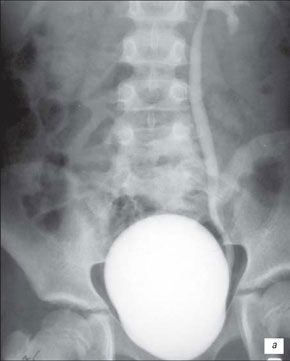

Екскреторна урографія хворого з двостороннім обструктивним мегауретритом

На екскреторній урографії ми спостерігаємо збільшення мисочок, розширення сечоводів, і змінену форму сечового міхура. Стінки якого мають бугристу, нерівну поверхню.